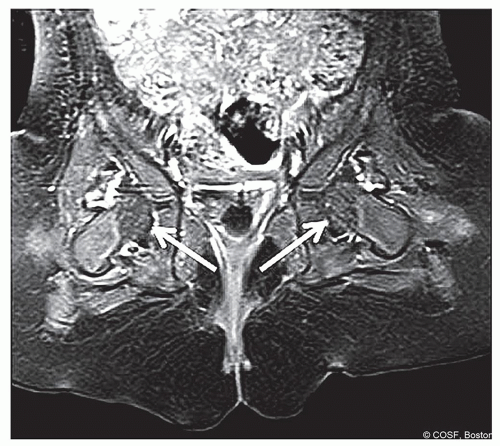

Evidence suggests that “global decreased enhancement” of the femoral epiphysis and/or hip abduction in cast greater than 60° correlates with the development of PFGD2 (Figures 20.10 and 20.11)

What if there is globally decreased enhancement? Assess the amount of hip abduction, amount of trochanteric molding, and relative difficulty maintaining the reduction

If any of the above are present, consider remaking the cast and/or conversion to open reduction

Figure 20-11 ▪ Postoperative contrast-enhanced magnetic resonance image (MRI) demonstrating global decreased enhancement of the left femoral epiphysis as noted by the arrows in agreement with the femoral epiphysis in Figure 20.7. (Courtesy of Children’s Orthopaedic Surgery Foundation.)